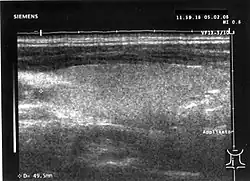

Eine vermutete oder vorhandene Vergrößerung der Schilddrüse kann mit Hilfe einer Schilddrüsensonographie bestätigt werden. Dabei zeigt sich ein im „gesunden“ Schilddrüsengewebe nicht vorkommendes inhomogenes Muster, bei dem sich echoarme und echoreiche Regionen abwechseln. Bei den echoarmen Regionen handelt es sich um die Entzündungsherde der Erkrankung. Sie stellen sich am Monitor dunkel dar, da sie den Schall schlechter reflektieren als normales Schilddrüsengewebe (siehe Untersuchung der Schilddrüse). Das Ausmaß der Schilddrüsengefäßversorgung, der Vaskularisation, lässt sich ebenfalls darstellen. Sie ist bei der subakuten Thyreoiditis de Quervain verringert bis normal.[16] Dies unterscheidet die Thyreoiditis de Quervain beispielsweise vom Morbus Basedow, bei dem die Vaskularisation wesentlich ausgeprägter ist.[16]

Subakute Thyreoiditis im Ultraschall: diffuse Echoarmut. -

Zum Vergleich: normale Echogenität der Schilddrüse -